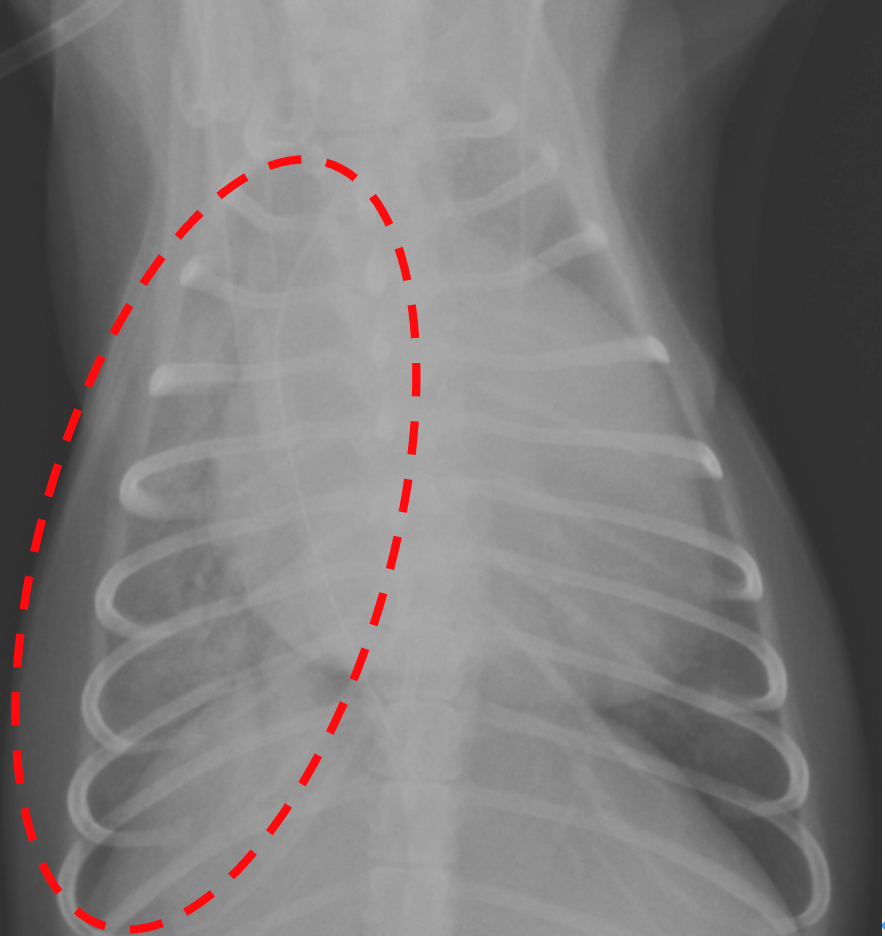

右肺の全域(点線)が白く、肺水腫が認められる。